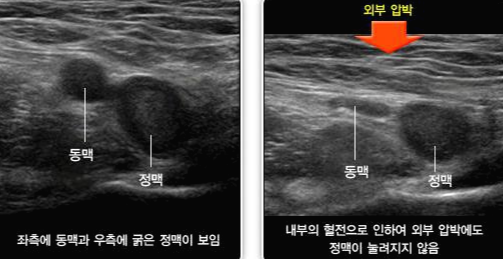

정맥류 검사는 하지 정맥류의 기능이나 구조를 평가하는 비 침습적 진단 검사입니다. 다리 정맥. 시험 도중 환자는 검사 테이블에 눕고 기술자는 다리의 피부에 젤을 바릅니다. 그 후, 변환기라는 휴대용 장치를 피부 위에 이동해 정맥과 주변 조직에서 반사하는 고주파 음파를 방출합니다. 이 음파는 모니터에서 볼 수 있는 화상에 변환됩니다. Leg Chamber Vein Exam은 정맥의 혈류를 평가하고 정맥 구조의 이상을 감지할 수 있습니다. 다리 깊은 정맥에 형성되는 혈전인 마음 부정맥 혈전증(DVT) 같은 상태를 진단하는데 도움이 됩니다. DVT는 바로 치료하지 않으면 목숨을 위협하는 상태에 빠질 가능성이 있습니다. 발에 바 정맥 검사는 다리에 통증, 부종, 불쾌감을 유발할 수 있는 풍만함, 왜곡된 정맥인 정맥류도 감지합니다. 발에 바 정맥 검사는 혈관 질환의 치료 선택 사항을 안내할 수 있는 유용한 진단 툴입니다. 상황. 예를 들어, 환자가 DVT진단을 받은 경우, 발에 바 정맥 검사는 혈전의 위치와 범위를 결정하는데 도움이 됩니다. DVT의 치료 옵션에는 혈액 희석제 또는 혈전 용해제가 포함되는 경우가 있고 다리에 바 정맥 검사 결과는 어느 치료 옵션이 가장 적합한지를 결정하는데 도움이 됩니다. 정맥 검사는 최상의 진료 프로세스를 결정하는데 도움이 됩니다.

정맥류 치료 옵션에는, 생활 습관의 변화, 압박 스타킹, 또는 경화 요법이나 정맥 레이저 치료 등 최소 침습 절차가 포함되는 경우가 있습니다. 하지심 정맥 검사 결과는 환자에게 최적의 치료 방법을 결정하는데 도움이 됩니다. 정맥류 검사는 안전하고 비 침습적인 진단 검사로 정맥의 기능이나 구조에 관한 유용한 정보를 제공합니다. 다리 정맥. 검사는 통상, 진료소와 병원 환경에서 열리고 특별한 준비는 필요 없습니다. 환자는 발에 접근이 쉬운 넉넉한 옷을 입어야 하고 검사 전에 피부에 로션이나 오일을 바르는 습관은 피해야 합니다. 결론으로서 발에 바 정맥 검사는 다음과 같은 중요한 진단 툴입니다. 심정맥 혈전증이나 정맥류 등의 혈관 상태 진단 및 치료 선택 사항을 안내합니다. 이 검사는 안전하고 비 침습적인 다리 정맥의 기능과 구조에 관한 귀중한 정보를 제공합니다. 발에 통증, 부종, 또는 불쾌감과 같은 증상이 나타나면 다리의 챔버 정맥 검사가 당신에게 적합한지를 담당 의사와 상담하세요.

정맥류 치료 옵션에는 생활 습관의 변화, 압박 스타킹 또는 경화 요법이나 정맥 내 레이저 치료 등의 최소 침습 절차가 포함될 수 있습니다. 하지심 정맥 검사 결과는 환자에게 최적의 치료 방법을 결정하는 데 도움이 됩니다. 정맥류 검사는 안전하고 비침습적인 진단검사로 정맥의 기능과 구조에 대한 유용한 정보를 제공할 수 있습니다. 다리 정맥. 검사는 일반적으로 진료소나 병원 환경에서 이루어지며 특별한 준비가 필요하지 않습니다. 환자는 발에 쉽게 접근할 수 있는 넉넉한 옷을 입어야 하며 검사 전 피부에 로션이나 오일을 바르는 것은 피해야 합니다. 결론적으로 족챔버 정맥검사는 다음과 같은 중요한 진단 도구입니다. 심부 정맥 혈전증이나 정맥류 등 혈관 상태 진단 및 치료 옵션을 안내해 드립니다. 이 검사는 안전하고 비침습적이며 다리 정맥의 기능과 구조에 대한 귀중한 정보를 제공할 수 있습니다. 다리에 통증, 붓기 또는 불쾌감과 같은 증상이 나타나면 다리 챔버 정맥 검사가 당신에게 적합한지 여부를 담당 의사와 상담하십시오.